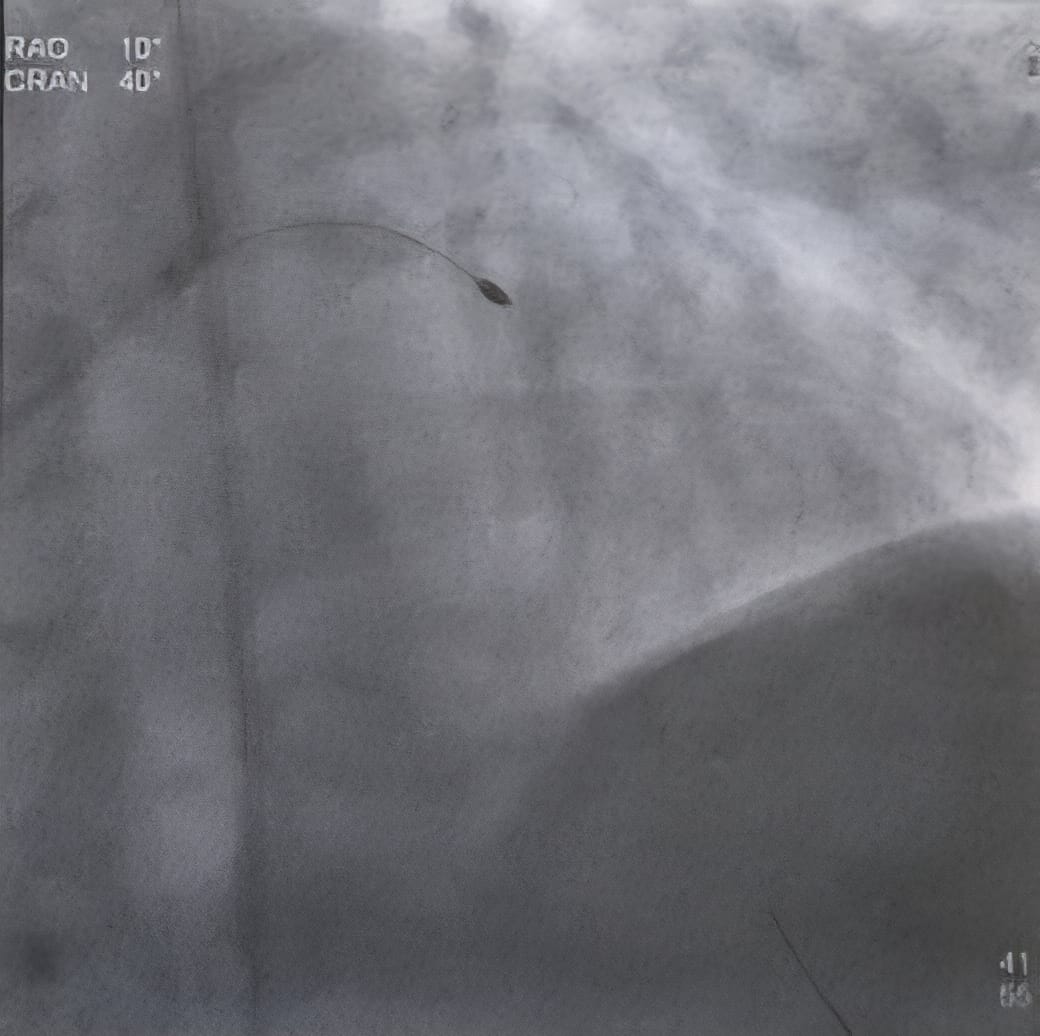

• Access: A catheter is inserted through the radial (wrist) or femoral (groin) artery.

• Guide Wire: A special guide wire is threaded across the blockage.

• Real-time imaging guides the device